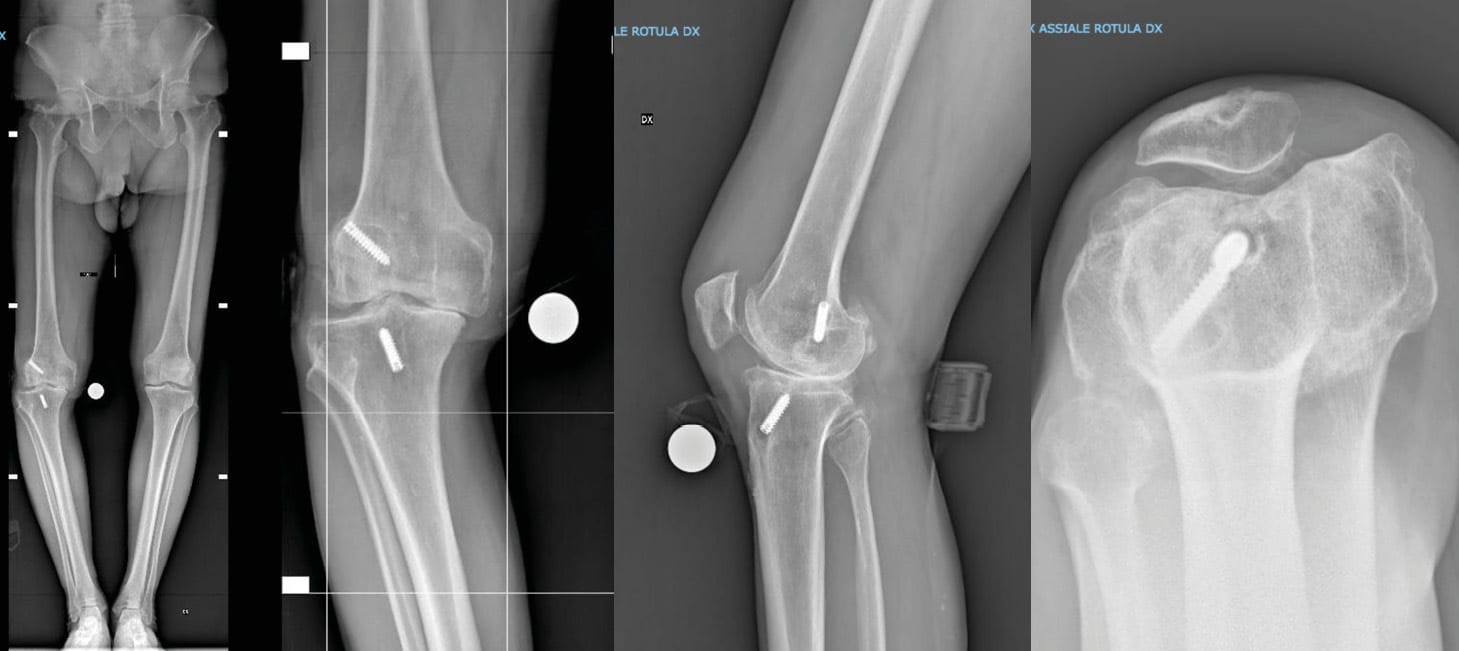

Radiographic evaluations were performed using anteroposterior, lateral, Rosenberg, sunrise, and full-length weight-bearing X-rays (Figure 1). From these, the mechanical hip-knee-ankle angle (mHKA), lateral distal femoral angle (LDFA), medial proximal tibial angle (MPTA), and arithmetic HKA (aHKA) classification were calculated [13] MacDessi SJ, Griffiths-Jones W, Harris IA, Bellemans J, Chen DB. Coronal Plane Alignment of the Knee (CPAK) classification. Bone Jt J 2021;103-B:329–37. https://doi.org/10.1302/0301-620X.103B2.BJJ-2020-1050.R1..

No patient required an osteotomy of the anterior tibial tuberosity due to reduced flexion and/or a low patella. Additionally, no patients required the use of cones or tibial augments, and no in-hospital complications were recorded in either group. Fixation devices were completely removed at the femoral level in 8 patients (22.9%), while they were left in place in 20 patients (57.1%). The remaining 7 patients (20%) exhibited resorption of the fixation devices (Figure 3).